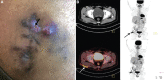

Fig. 5

(A) Clinical photograph of a 30 yr old male, showing right-sided post-injection gluteal abscess (black arrow) in a patient with NTM infection. (B) Transaxial fused 18F-fluorodeoxyglucosepositron emission tomography-computed tomography (18F-FDG-PET-CT) image of the same patient, at the level of acetabulum showing FDG accumulation in the subcutaneous thickening and stranding (arrow) involving the underlying right gluteus muscle superficially in right gluteal region. Source: Reproduced with permission from Ref. .